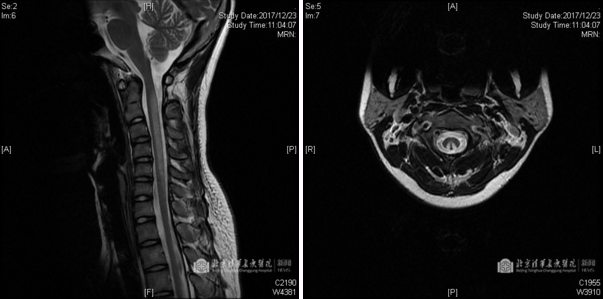

自2017年开始,笑气逐渐进入大众的视野,被人们所知晓。不断有媒体报道年轻的中国留学生因为吸食笑气导致下半身瘫痪,回国治疗的事情。那么笑气是如何致病的?其原因和机制尚未完全明确。目前公认的理论是,笑气可使维生素B12(钴胺素)的钴离子发生不可逆的氧化反应,使钴胺素失去活性。钴胺素是核蛋白合成及髓鞘形成所必需的辅酶。长期慢性滥用笑气致使神经系统严重脱髓鞘,临床表现为贫血,周围神经及脊髓后索的病变,核磁影像学可见颈髓平面背侧高强化影,呈对称“倒V字”型(兔耳征),严重者出现双下肢瘫痪甚至死亡。

上图示颈段脊髓背侧长节段异常信号,横断面可见对称的倒V型